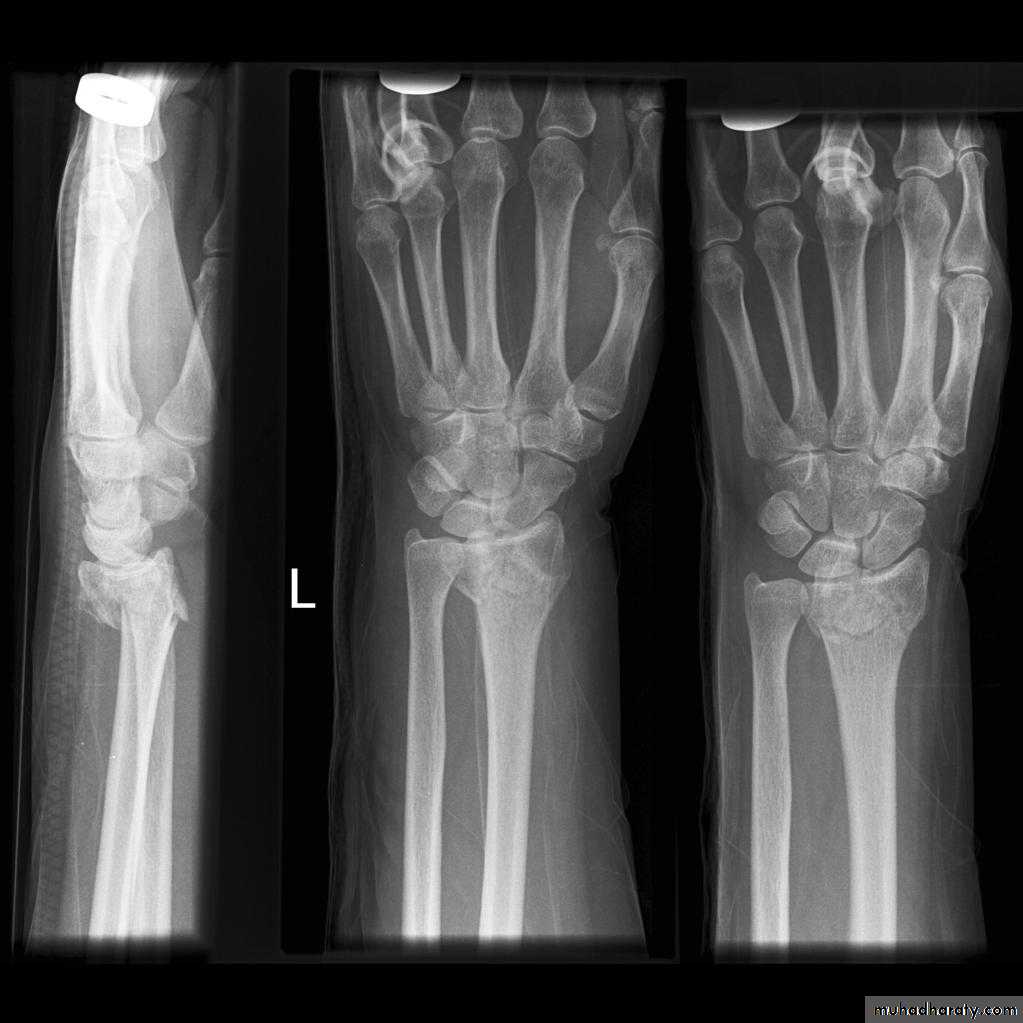

Upper limb

Fall on out stretched hand

xray

Hand deformity